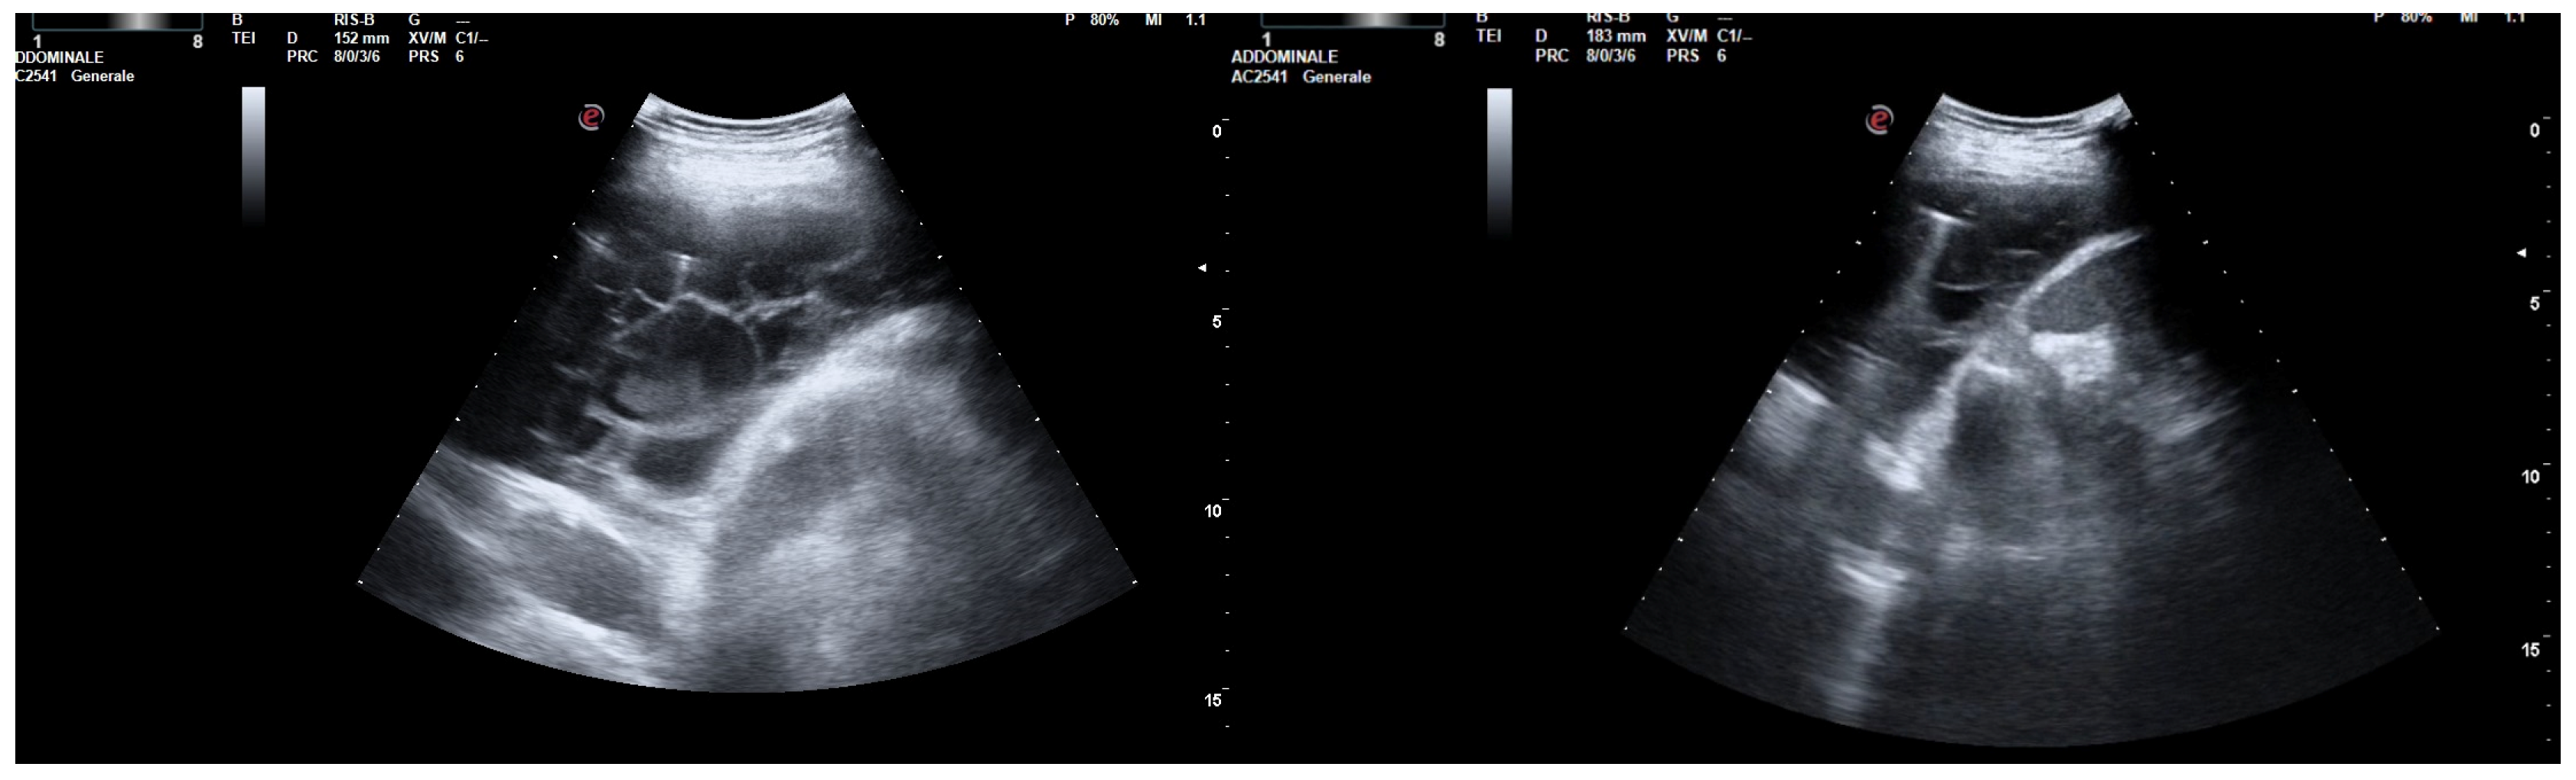

After the placement of a chest tube, pleural fluid samples were sent for microbiological and physicochemical analysis, which confirmed the diagnosis of pleural empyema. Two days after the placement of the chest tube, the fluid flow decreased. To break up the fibrin pockets present in the empyema and promote the complete evacuation of the fluid, irrigation of the pleural cavity with 200,000 UI of urokinase in 50 mL of saline solution was performed under US guidance (Figure 2).

After a chest CT scan, which showed a massive effusion, the patient underwent a thoracoscopic lavage of the left pleural cavity without any complications. At the end of the surgery, two left thoracic drains were left in place, through which repeated irrigation of the pleural cavity with urokinase was performed under serial US and radiological monitoring in the following days (Figure 4). At the same time, empiric antibiotic therapy with piperacillin/tazobactam and teicoplanin was initiated. During his hospitalization, the patient remained stably apyretic, with a progressive improvement of pulmonary gas exchange and the normalization of his inflammation biomarkers. Subsequently, the FiO2 was gradually titrated until the complete discontinuation of oxygen therapy.

In this scenario, fibrinolysis was performed after a uniportal VATS because of the persistence of fibrinous septa visualized using US and the slow outflow of fluid into the drainage bag. The irrigation of the pleural cavity was conducted with 200,000 UI of urokinase in 50 mL of saline solution. This was followed by the closure of the chest drain for 2–4 h, and then it was reopened. Irrigation was performed every 48 h for 3 days. On day 5, the absence of fibrinous septa and the small amount of fluid on the patient’s chest US allowed for the removal of the drain and his discharge from the hospital.

Figure 2. Chest US during pleural lavage with urokinase. Star: distal end of chest drain; Arrow: spread of fluid.

Figure 4. Complex and septated pleural effusion after VATS treated with IPFT.